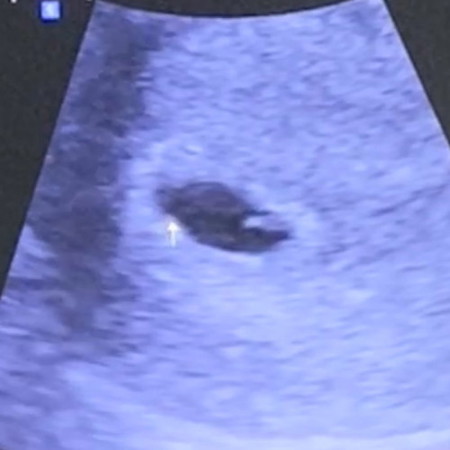

เเม่ๆซาวด์เจอตัวน้องเเละหัวใจตอนกี่วีคค่ะ บ้านนี้ถ้านับจาก ปจด ครั้งสุดท้าย 6w2d ยังไม่เจอน้อง เจอเเต่ถุงตั้งครรภ์ เเละหมอเห็นน้องถุงไข่เเดง หมอนัดอีก 3W ไปซาวด์ใหม่ค่ะ